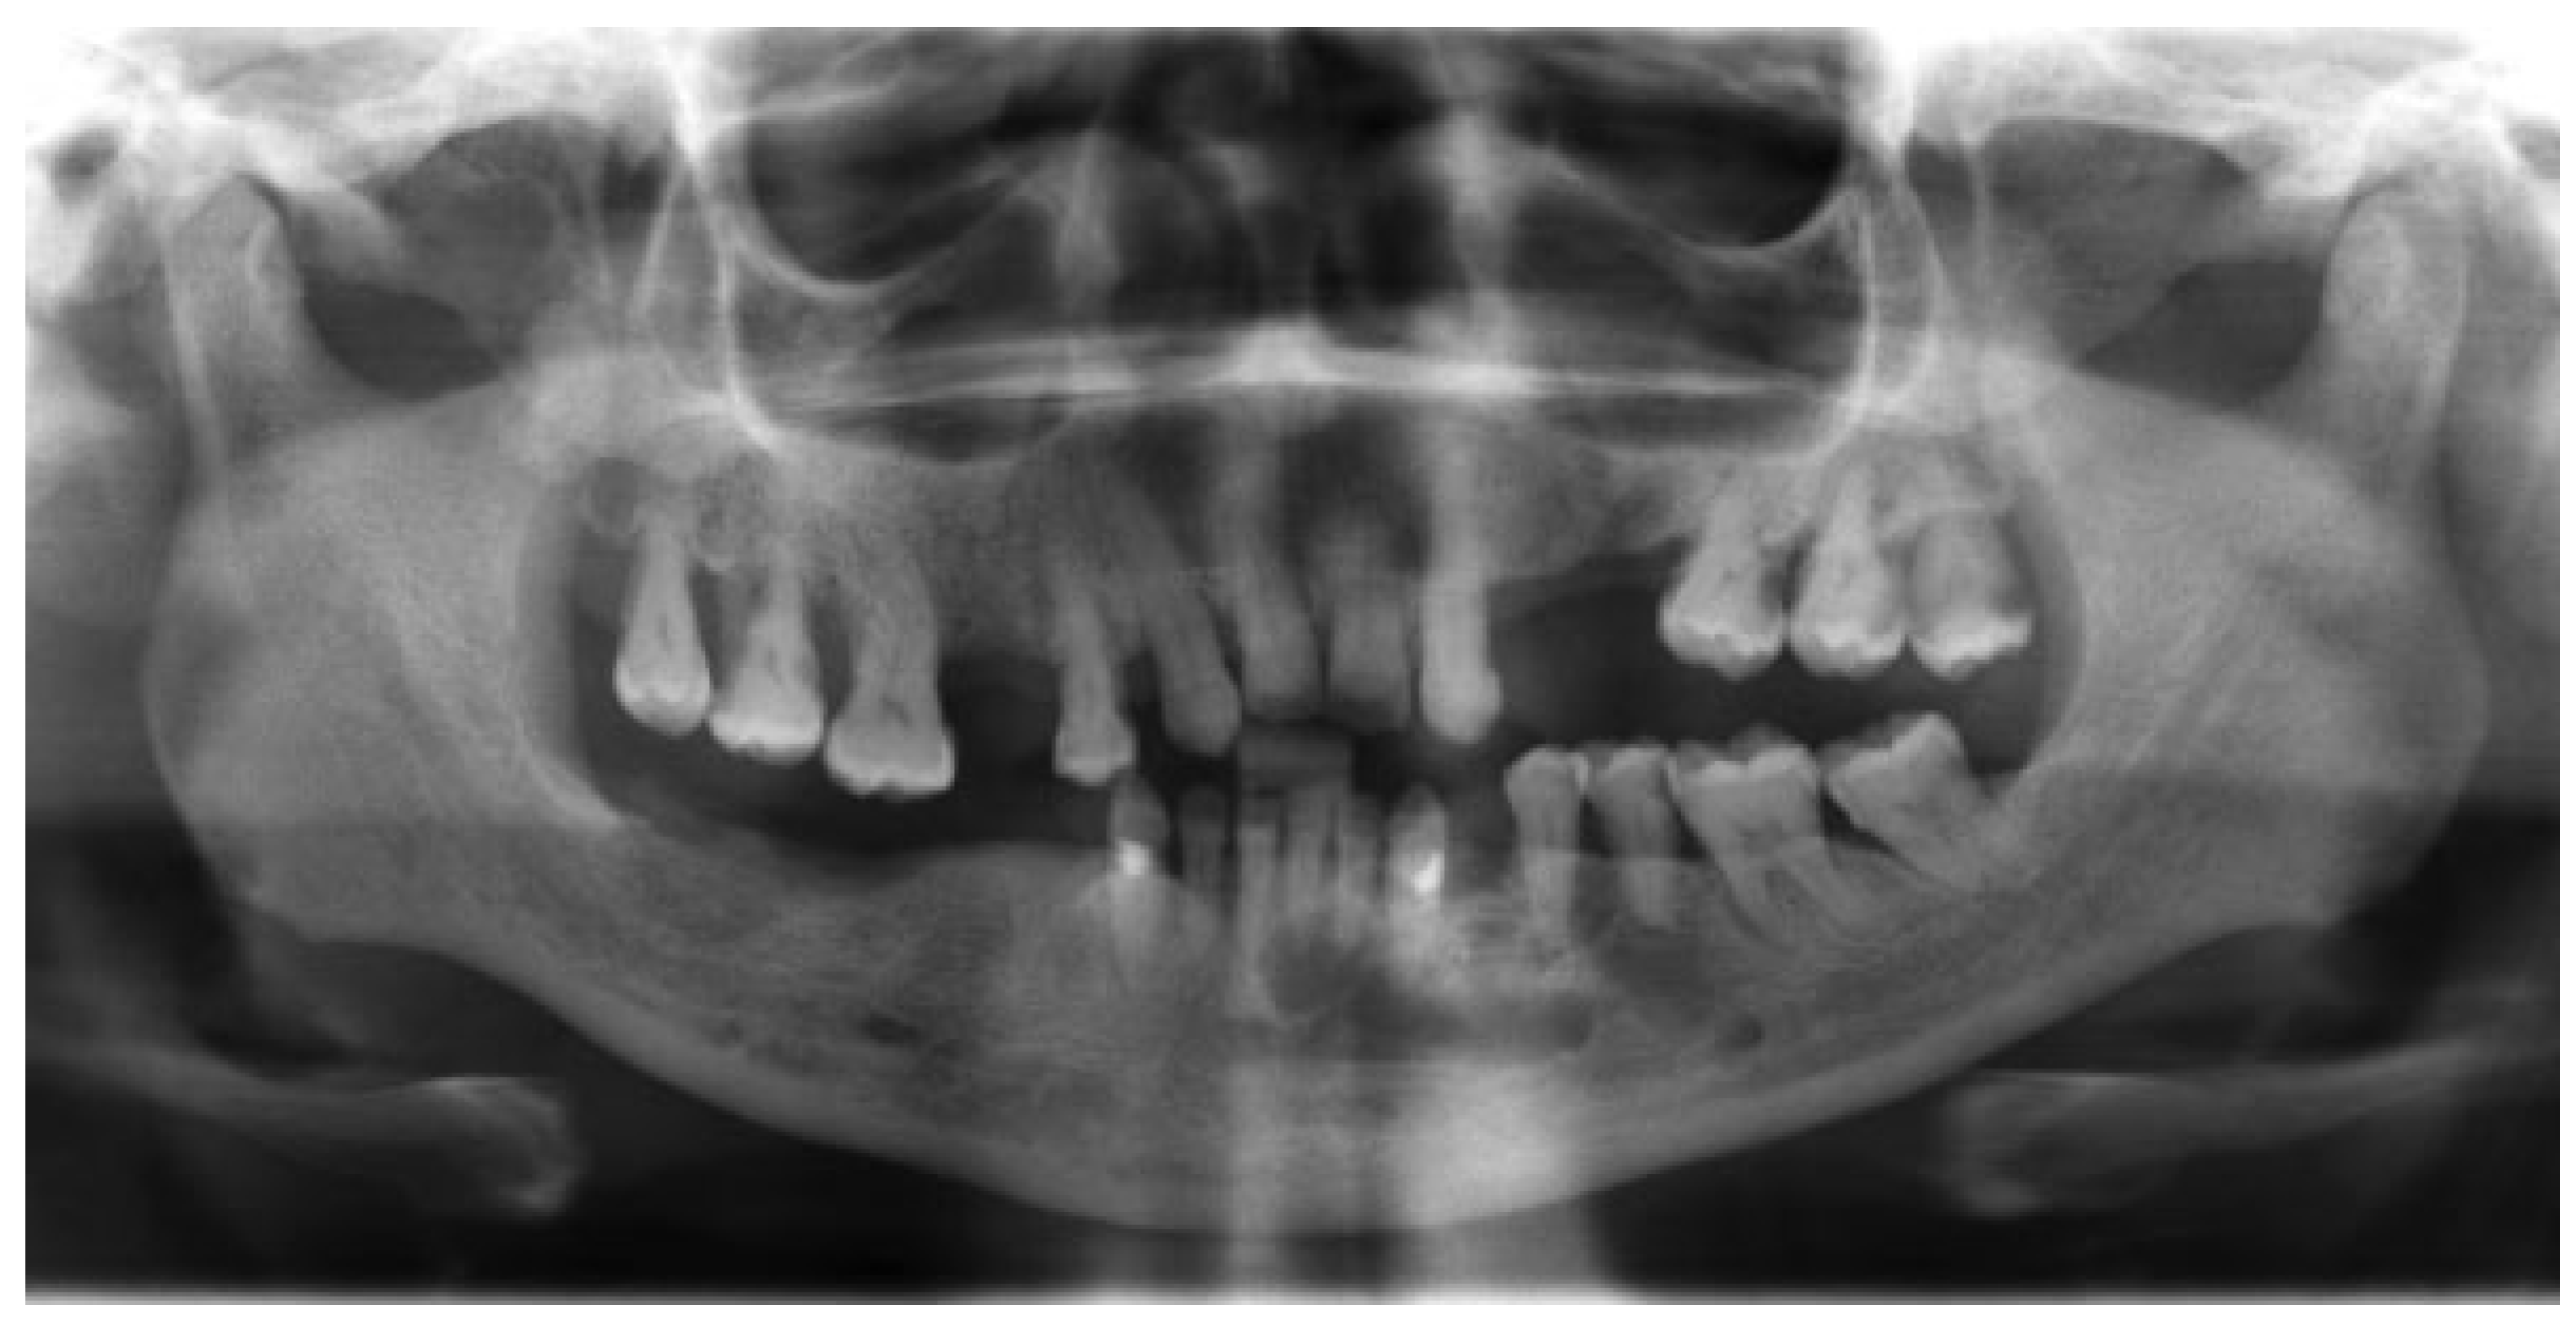

The third case was a 29-year-old white male with an expansile lesion of the anterior mandible. Panoramic radiograph showed a multilocular lesion involving the inferior border of the mandible and extending from the left second molar to the right canine (Figure 1). Incisional biopsy proved this lesion to be an ameloblastoma. The treatment plan included mandibular resection with 1-cm margin and immediate reconstruction with a free fibula microvascular flap. A tracheostomy for airway protection was also planned. A high-resolution CT scan was obtained followed by construction of a model. A custom prebent plate was obtained using the model as a reference. Using a combined transoral and transcutaneous approach, the mandible was resected from the left angle through the right second bicuspid. The 2.4-mm prebent reconstruction plate was placed (Figure 2). A free microvascular fibula flap with a skin pedicle was harvested. The fibula was contoured and adapted to the inner aspect of the custom-bent plate and secured with nonlocking screws (Figure 3). The skin pedicle was used to close the resulting soft tissue defect at the floor of the mouth. A tracheostomy was performed at the end of the case. The total surgical time including all the procedures was 10 hours and 33 minutes.

Figure 1. Panoramic radiograph showing large expansile multilocular radiolucent lesion. Case 3.